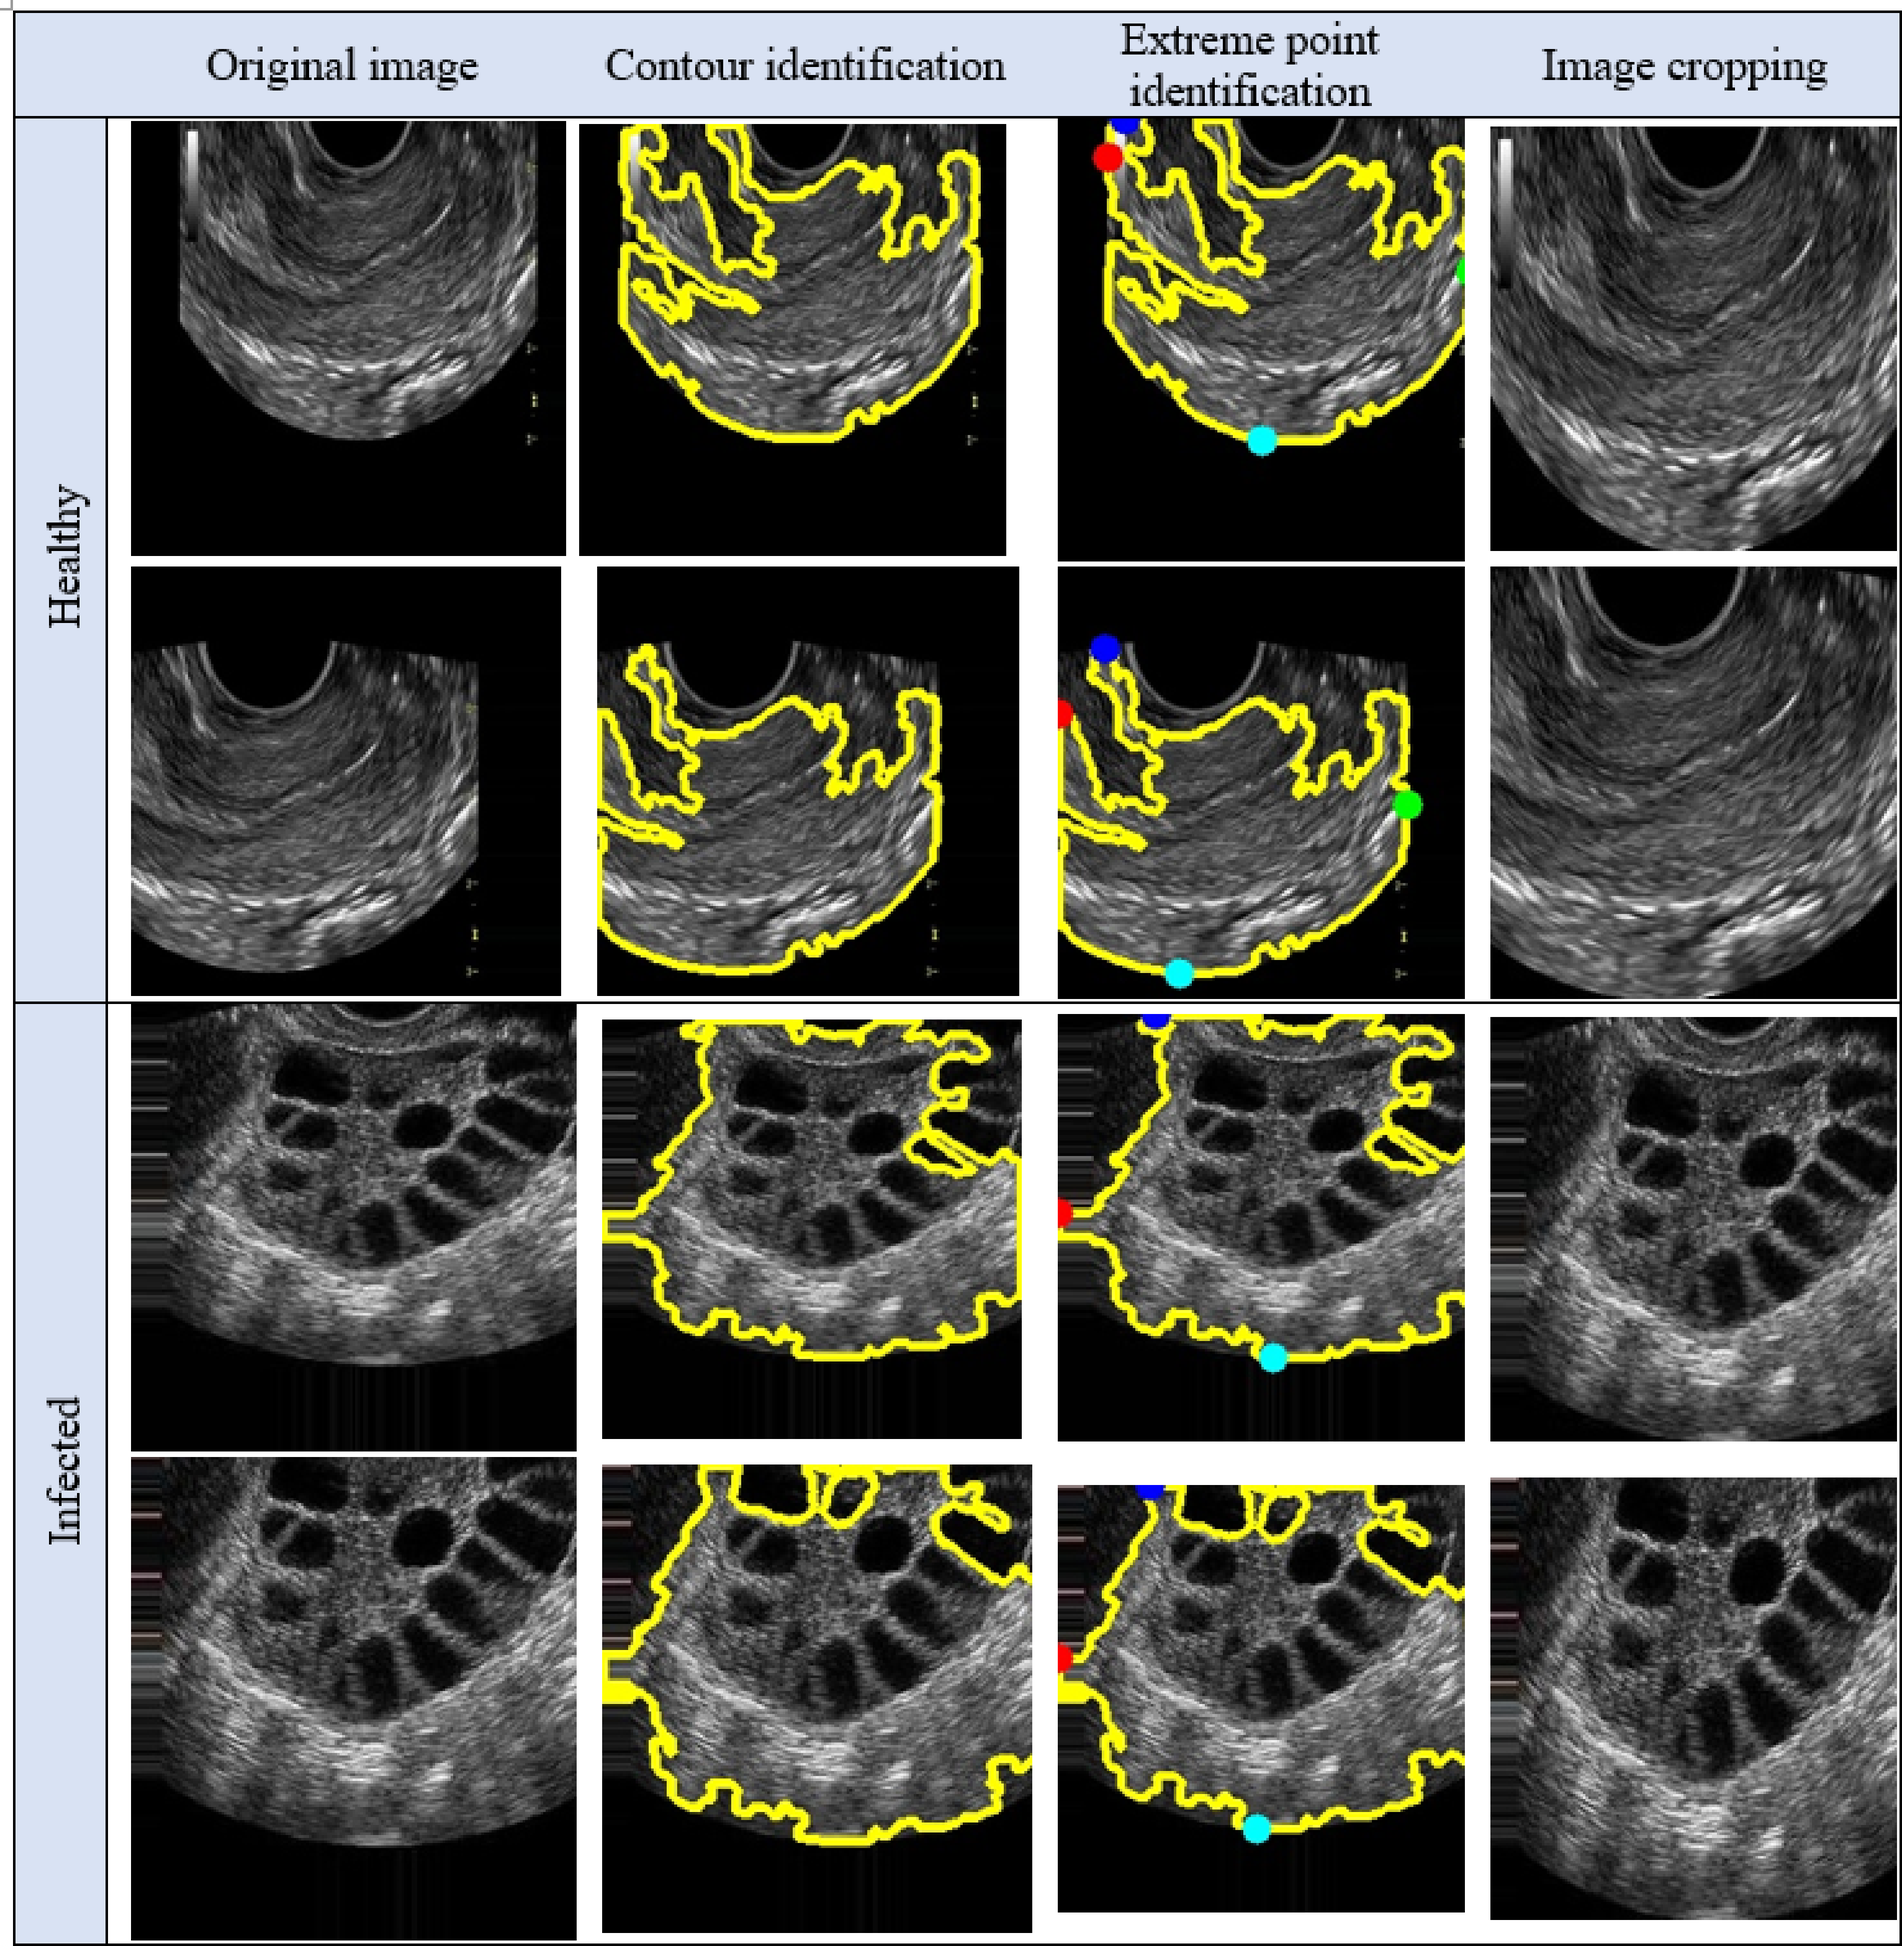

Step by step breakdown of cropping the image.